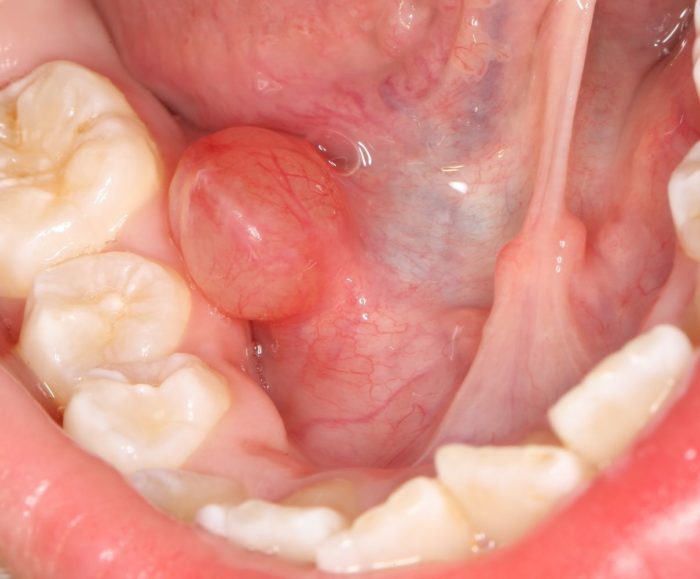

Гемангиомы.

Самые распространенные опухоли полости рта. В 90% случаев гемангиомы диагностируются сразу или в ближайшее время после рождения ребенка. Бывают простыми (капиллярными), кавернозными, капиллярно-кавернозными и смешанными. Отличительной особенностью этих опухолей полости рта является их побледнение или уменьшение в размерах при надавливании. Травмирование гемангиом часто приводит к кровоточивости.

Лимфангиомы.

Возникают в результате нарушений эмбриогенеза лимфатической системы и выявляются обычно у новорожденных. Характеризуются образованием ограниченной или диффузной припухлости в полости рта. Среди опухолей полости рта различают кавернозные, кистозные, капиллярно-кавернозные и кистозно-кавернозные лимфангиомы. Эти опухоли полости рта склонны к воспалению, которое часто бывает связано с травмой слизистой рта или обострением какого-либо хронического воспалительного заболевания носоглотки: пульпита, периодотита, хронического тонзиллита, гайморита и пр. Отдельные авторы указывают также на связь рецидивирующего воспалительного процесса в лимфангиоме с обострениями хронического гастрита, дуоденита или колита.